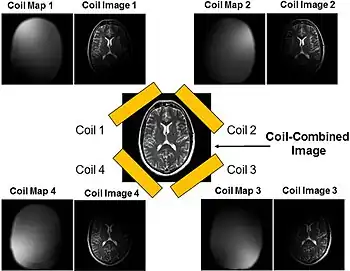

Parallel imaging

Parallel imaging involves the addition of multiple coils surrounding the target with each coil acquiring a fraction of the total image. Because modern GPUs have parallel processing capabilities, they can reconstruct each portion of the image simultaneously. Therefore, the more coils used, the faster the acquisition of the MR images.[15]